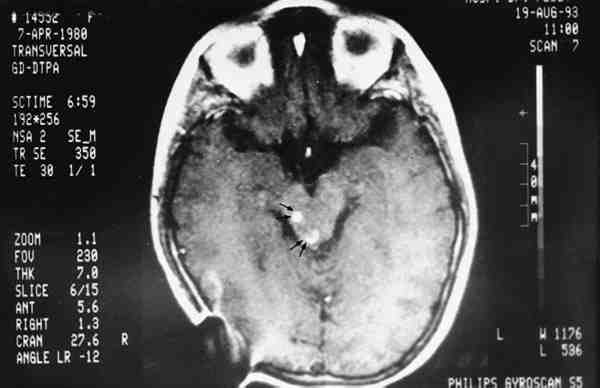

Figura 9

LESIONES GOMATOSAS (HIPERDENSAS TRAS INYECTAR CONTRASTE) A NIVEL MESENCEFÁLICO. NO HAY PATOLOGÍA EN LOS NERVIOS ÓPTICOS. IMAGEN DE TAC.